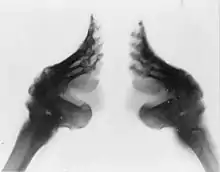

Foot binding, a practice commonly inflicted on Chinese women between the 10th century and the early 20th century. The image shows an X-ray of two bound feet.

The status of women in China was also low, largely due to the custom of foot binding. About 45% of Chinese women had bound feet in the 19th century. For the upper classes, it was almost 100%. In 1912, the Chinese government ordered the cessation of foot-binding. Foot-binding involved the alteration of the bone structure so that the feet were only about four inches long. The bound feet caused difficulty in movement, thus greatly limiting the activities of women.